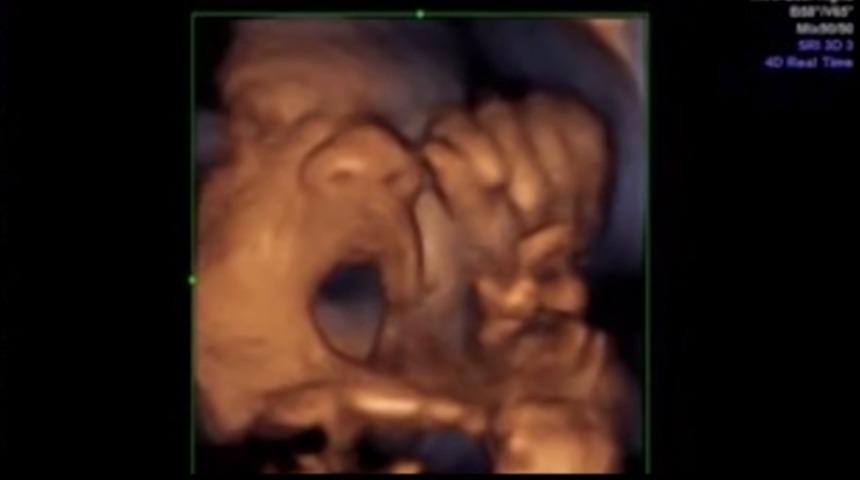

Fetüsler ağız ve dillerini, konuşuyor veya şarkı söylüyormuş gibi hareket ettirdiler. Sadece video büyüleyici değil, araştırma da önemli. Bu yeni teknikle, çocuğun sağır veya işitme engelli olduğu hamileliğin erken döneminde saptanabilir. Bu sayede ailelere çocuk doğmadan öne hazırlanmaları için zaman verilmiş olur.